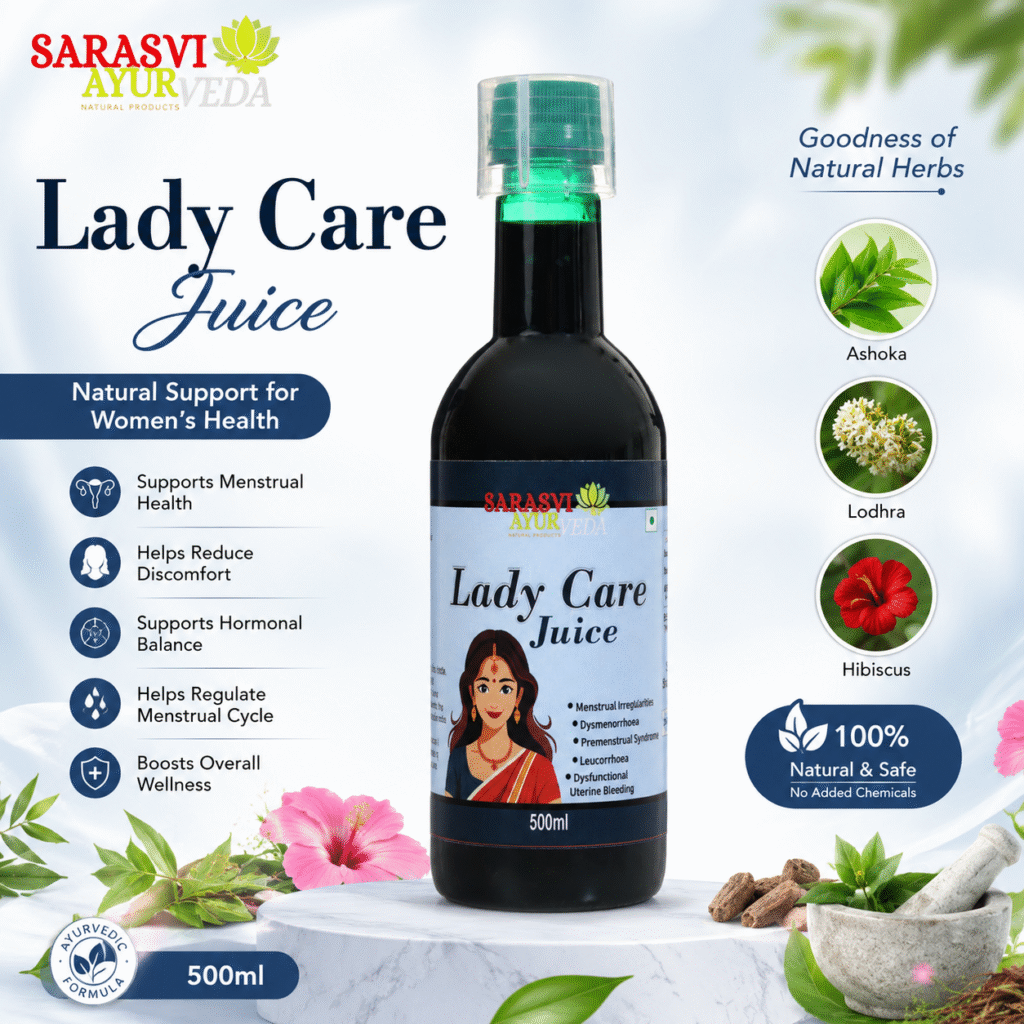

What is Lady Care Juice?